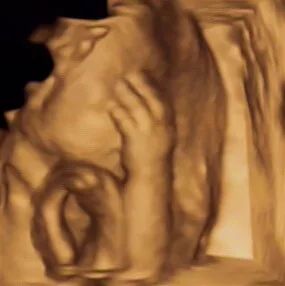

超声影像(四维彩超)的立体成像效果及清晰度,受孕妈胎位情况及宝宝的配合程度而定。

能否与宝宝面对面,这取决于胎宝宝在做超声那会儿的身体姿势,如果胎宝宝正面对你,并且五官周围羊水很充足,那简直是太幸运了,能看到清晰的五官。

但是如果胎宝宝正好脸背着你,或者脸部周围羊水不多,胎宝宝因皮肤呈皱褶状态,还有层胎脂保护着宝宝,在超声采集相片时,会影响图片的清晰度。还有部分胎宝宝的头部位置比较低,头在骨盆内,孕妈骨盆的骨骼会干扰我们的四维仪器,导致胎宝宝面部图像模糊。